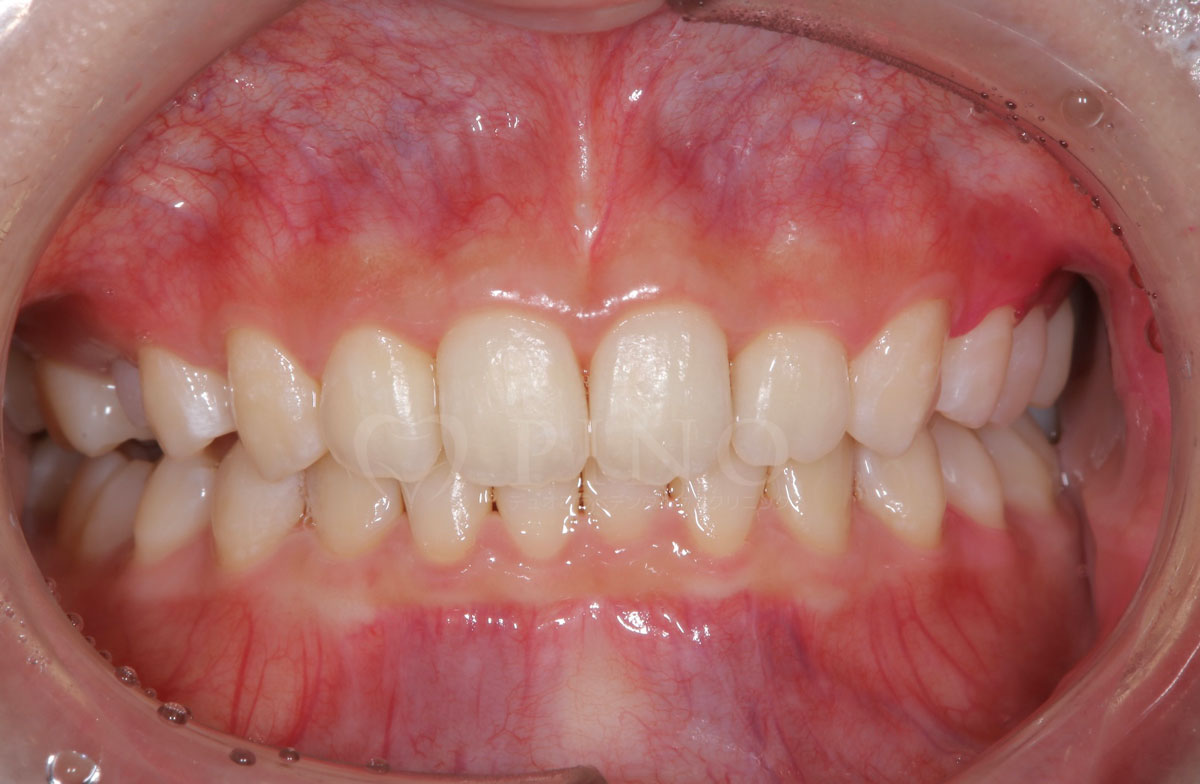

症例8:歯が全体的にガタガタして気になる(30代女性)

主訴 歯が全体的にガタガタして気になる 診断名 上下顎1級叢生 治療方法 マウスピース全顎矯正 抜歯 あり 上2本 オルソパルス あり 治療期間 1年5ヶ月 費用 891,000円+補綴治療費(セラミック320,000円) 副作用・注意点 歯を抜く際に痛みを伴う可能性がある、矯正後後戻りを防ぐためリテーナーの使用が必要となる -